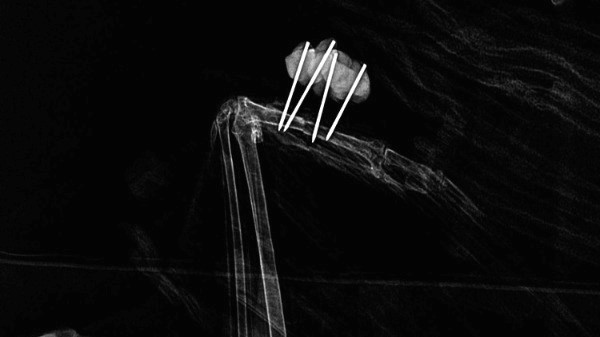

This was taken intraoperatively, as you can see owl’s body overlying the wavy heating element of the heat pad. Because it can sometimes be difficult to correlate what is palpable to actual bone orientation, the surgical clamp seen was used as a landmark. Comparing its physical location to what is seen on the radiograph can help improve alignment.

It is simply amazing to be able to do this without having to break sterile field or otherwise disturb an anesthetized patient, which would be the case with a typical standing x-ray machine.

The “after” photo: both metacarpal bones are well-aligned!